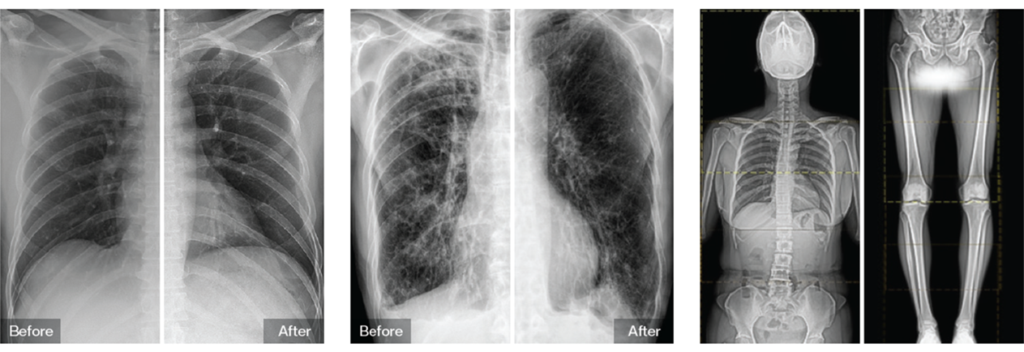

- Clinical Image Processing

It features professional tools such as bone suppression for soft tissue visualization. It also covers scatter reduction for enhanced contrast and image stitching for whole spine and long bone imaging.